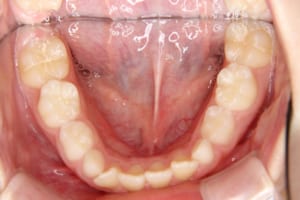

治療前

• 前歯の叢生、上顎前突の症例です

• 上の前歯が出ていることを主訴に来院しました

• 上顎前突、前歯の叢生があります

• 側切歯がねじれて生えています

• 前歯部に叢生があります